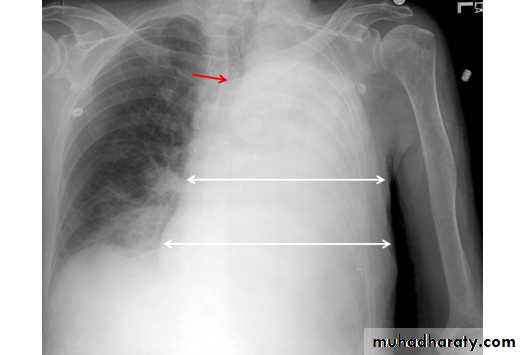

Left upper lobe collapse has distinctive features but can be challenging to identify on chest radiographs by the uninitiated.

Radiographic features

The left upper lobe collapses anteriorly becoming a thin sheet of tissue apposed to the anterior chest wall, and appears as a hazy or veiling opacity extending out from the hilum and fading out inferiorly . It thus reverses the normal slight increase in radiographic density seen as you move down the lung (due to increased thickness of the chest soft tissues).

Parts of the normal cardiomediastinal contour may also be obliterated where the left upper lobe, particularly the lingula abut the left heart border. The anterior parts of the aortic arch are also often obliterated from view.

In some cases the hyperexpanded superior segment of the left lower lobe insinuates itself between the left upper lobe and the superior mediastinum, sharply silhouetting the aortic arch and resulting in a lucency medially. This is known as the HYPERLINK "http://radiopaedia.org/articles/luftsichel-sign" luftsichel sign.

The left hilum is also drawn upwards, resulting in an almost horizontal course of the left main bronchus and vertical course of the left lower lobe bronchus.

Non-specific signs indicating left sided atelectasis will also be present, including:

elevation of the hemidiaphragm

'peaked' or 'tented' hemidiaphragm: HYPERLINK "http://radiopaedia.org/articles/juxtaphrenic-peak-sign" juxtaphrenic peak sign

crowding of the left sided ribs

shift of the mediastinum to the left

On lateral projections the left lower lobe is hyperexpanded and the oblique fissure displaced anteriorly. There is associated increase in the retrosternal opacity.